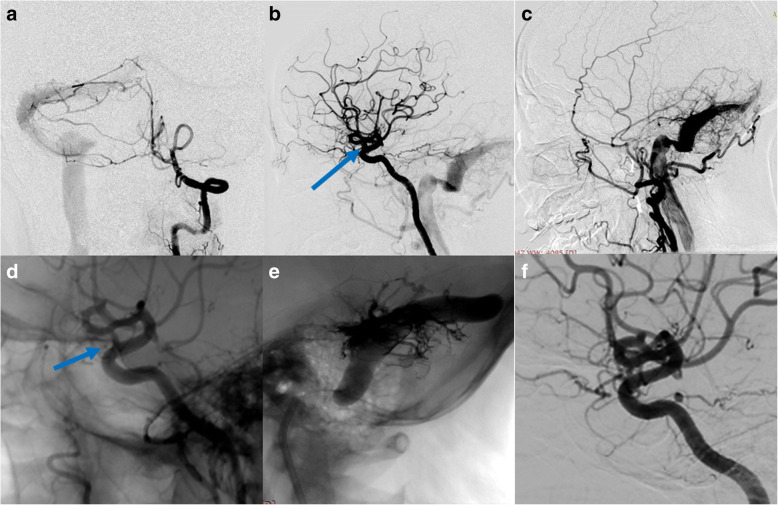

Case No. 4 was 34-year old female complained a gradually aggravated headache for 3 months. DSA showed a V-B junction aneurysm. Besides the aneurysm, the patient suffered from an AVM (Spetzler-Martin 3) that received feeding arteries both from the anterior posterior circulation (Fig. 4a, b). We deployed the PED (4.25 mm*25 mm) from the lower 1/3 of basilar artery to the left VA and further coiled the aneurysm loosely to achieve favorable stasis of flow (Fig. 4c). 3 months follow up indicated incomplete occlusion of the aneurysm (Fig. 4d). Case No. 5 was an 8-year-old girl presented with ataxia, vomiting and nausea. DSA indicated a large V-B junction dissecting aneurysm (Fig. 5a). Learned from the experience of case 4, we decided to telescoping two PEDs (4.25 mm*35 mm) to achieve a better flow diversion effect. Control angiography suggested that there was no apparent stasis of angiographic agent due to the persistent blood flow from the contralateral VA. So we decided to coil the aneurysm and concomitantly to occlude the aneurysm with a detachable balloon (Balt, France) (Fig. 5b). The patient recovered from general anesthesia smoothly and discharged without any neurological deficit. 3 months follow up angiography indicated a certain degree of decrease in size and the patient was free from any symptom, yet the aneurysm was still partially embolised (Fig. 5c). So, knowing that the V-B junction aneurysm is quite refractory in nature, we treated case No. 6 (Fig. 6a) By overlapping 2 longest PEDs (4.25 mm*35 mm) to enhance the flow diversion effect and further occluded the contralateral VA with coils (Fig. 6b, c). It is inevitable to cover the perforating branches of basilar artery if you chose a 35 mm long PED. The patient experienced transient visual loss of both eyes, however, the patient completely recovered from these symptoms one day after operation. This patient is still on follow-up.

Fig. 4.

Case No. 4 has a V-B junction aneurysm with coexisting AVM supplied by both anterior (a) and posterior circulation (b). We deployed the PED from the lower 1/3 of basilar artery to the left VA and further coiled the aneurysm loosely (c). 3 months follow up indicated incomplete occlusion of the aneurysm (d)

Fig. 5.

Case No. 5 was an 8-year-old girl with a large V-B junction dissecting aneurysm (a), we overlapped two PEDs, coiled the aneurysm and sacrificed the left VA with a detachable balloon (b). At 3-month follow-up, the aneurysm was still patent but decreased in size (c)

Fig. 6.

Case No. 6, a V-B junction aneurysm (a) treated by overlapping 2 longest PEDs (4.25 mm*35 mm) (b) to enhance the flow diversion effect and further occluded the contralateral VA with coils (c). Note that the distal PED covered the mid-basilar perforators